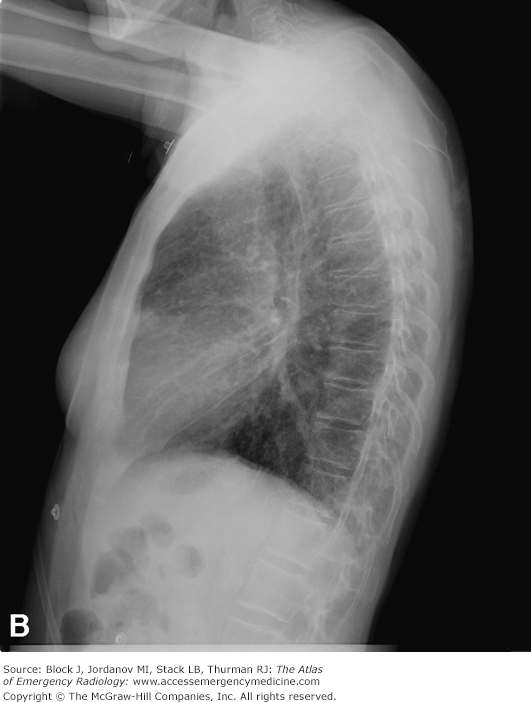

Frontal and lateral views of the chest demonstrate airspace disease on the lateral film (B) in the right lower lobe (white arrow) that may not be immediately apparent on the frontal film (you can see the pneumonia in the right lower lobe in [A] [black arrow]).

In this case, a right lower lobe pneumonia superimposed on the lower spine on the lateral view makes the spine appear “whiter” (more dense) just above the diaphragm. This is called the spine sign.